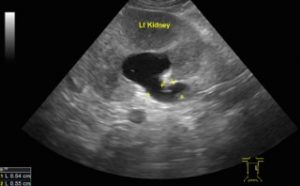

1レントゲンや超音波画像診断で、結石の位置と大きさ、数(一個とは限らない)を確認。超音波検査(エコー検査)を実施すると腎盂という部分が拡張し、尿管の太さもが大きくなっている所見が見られます。このような所見は、どこかで尿管が詰まっています。その原因は「尿管結石」が多いのですが、その他にも腫瘍の発生を含め様々な原因が考えられます。

しかし、詳細な超音波検査の結果、尿管結石が併発していることが判りました。

すでに腎臓から尿が流れ出ずに腎臓が膨れはじめています。このままでは腎機能はどんどん低下しついには「水腎症」となり「尿毒症」となってしまいます。

今回は充分に超音波画像診断を実施し、1箇所かつ片側のみの尿管結石と判断し、